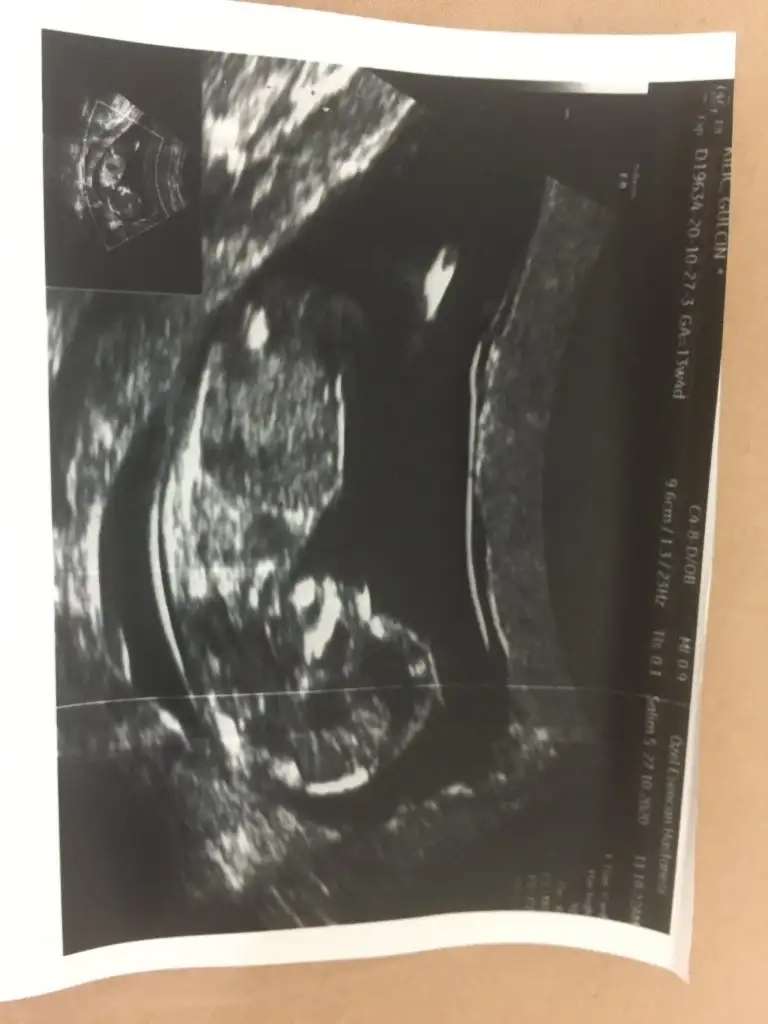

Kesinlikle erkekCnm daha önce atmıştım arkadaşımın Buda 13+ 2 yorularmısınIkra meyra

O 12. Hafta ultrasonuydu canım.16. Haftadayım kızım olacak inşallahYüksek ihtimal erke

Tebrik ederimO 12. Hafta ultrasonuydu canım.16. Haftadayım kızım olacak inşallah![]()

Size 12.haftada doktor, erkek mi dedi?O 12. Hafta ultrasonuydu canım.16. Haftadayım kızım olacak inşallah![]()